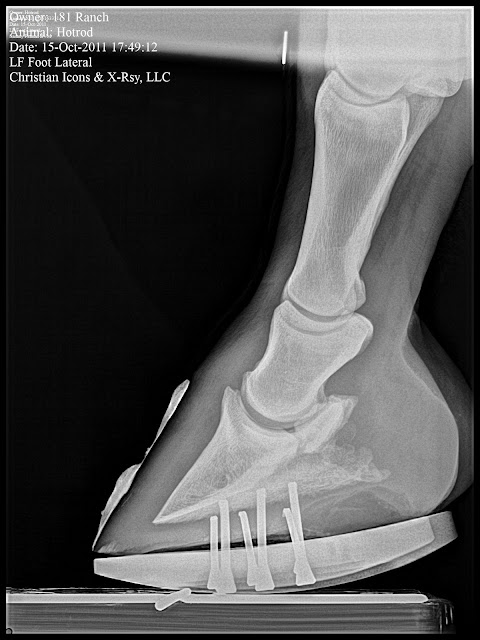

This case was a grade 2 club. The owner reports the horse had a check ligament desmotomy at 18 months and is now 2 years. Note the Large bone angle in the Left Front and the boney changes that accompany the club foot forces, bump on dorsal aspect of coffin bone about halfway down and remodeled apex. All load induced lesions. This case is a barrel horse prospect and not actively training that much. Dr. Redden decided to maintian in four point trim for now and is needed to help maintain good foot mass while in performance a rockered flat steel shoe and or a full rocker.